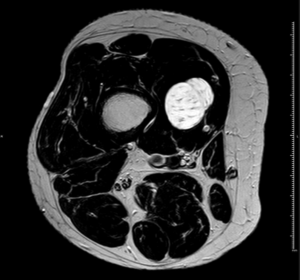

RM axial T1 con supresión grasa y gadolinio iv.

HALLAZGOS RADIOLÓGICOS